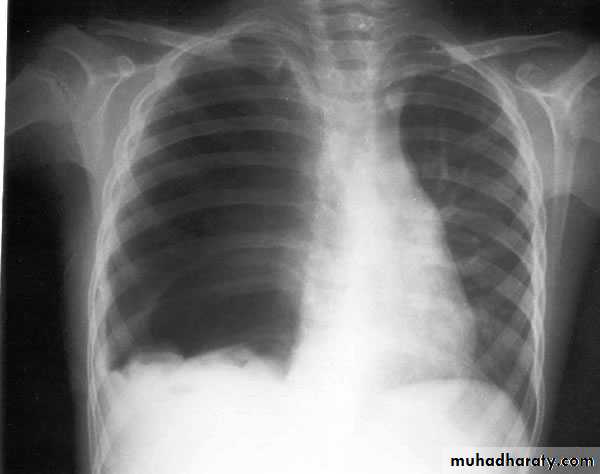

X-ray hemothorax

X-ray pneumohemothorax